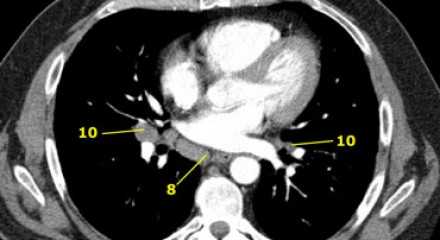

8. Параэзофагеальные лимфатические узлы

Эти лимфатические узлы ниже подкаринальных лимфатических узлов и распространяются каудальнее до диафрагмы. На изображении слева ниже уровня карины справа от пищевода обозначен лимфатический узел 8 группы.

7. Подкаринальные лимфатические узлы

Эти лимфатические узлы расположены ниже уровня бифуркации трахеи (карины), но не относятся к нижнедолевым бронху и артерии. Справа они располагаются каудальнее нижней стенки промежуточного бронха. Слева они располагаются каудальнее верхней стенки нижнедолевого бронха. Слева лимфатический узел 7 группы справа от пищевода.